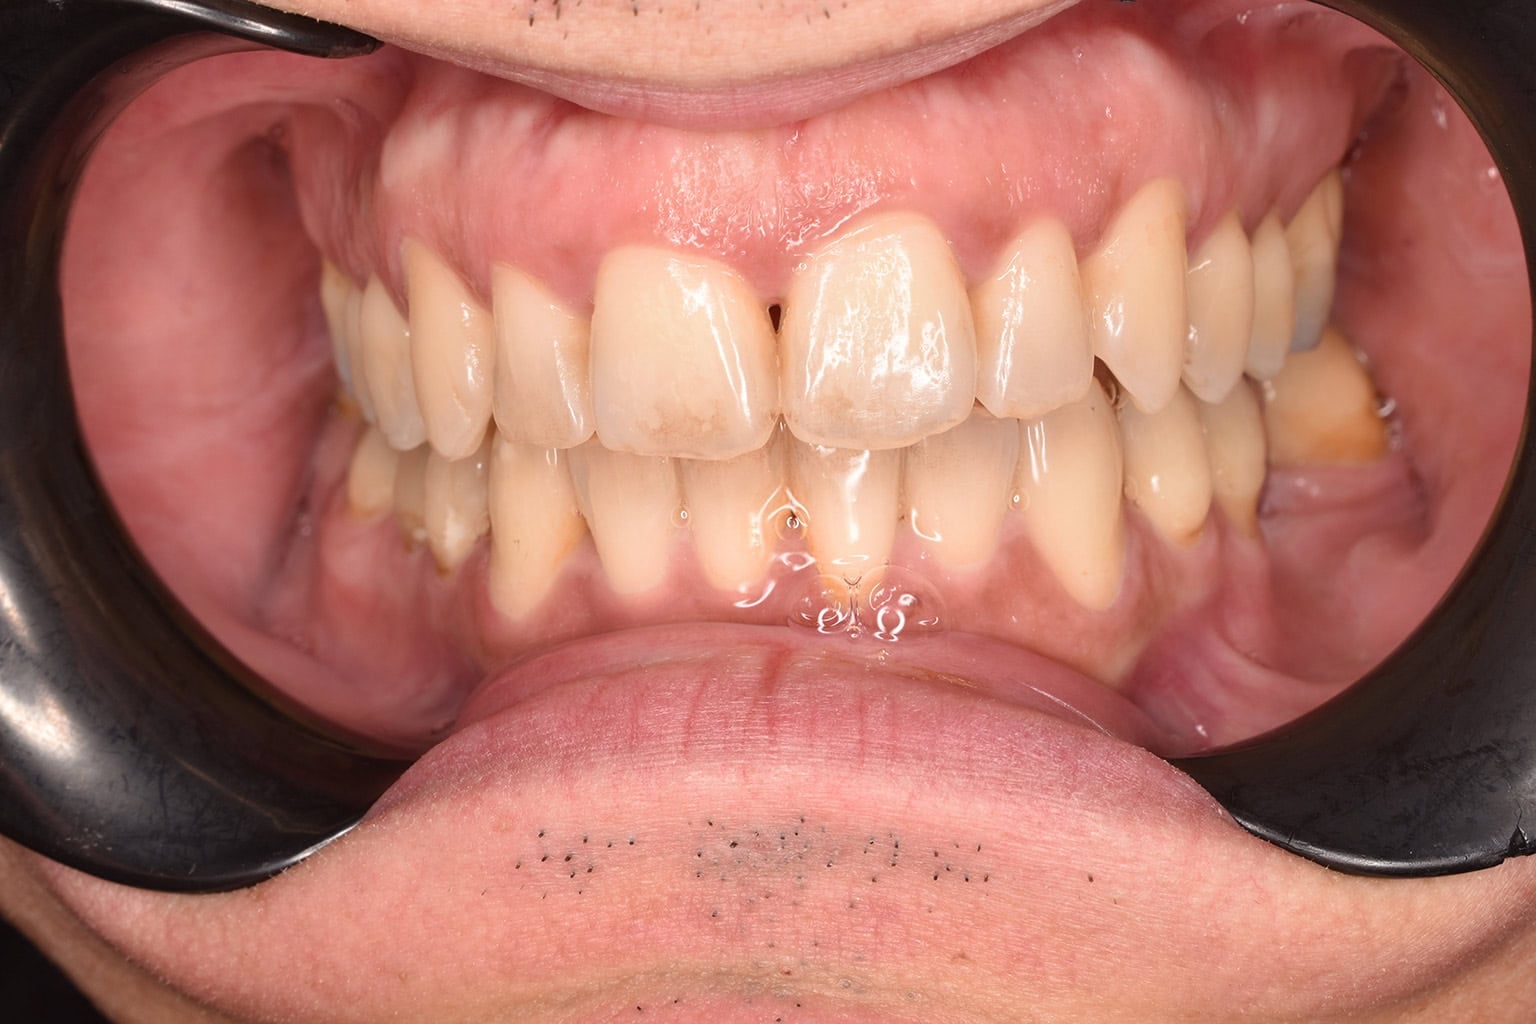

Vorher-Nachher-Ergebnisse

Echte Ergebnisse. Echte Menschen.

Jede Behandlung bei TIEFBLAU Kieferorthopädie ist so individuell wie der Mensch dahinter. In unserer Vorher-Nachher-Galerie zeigen wir Ihnen echte Behandlungsergebnisse aus unserer Praxis in der Kölner Südstadt: Schonend erzielt, präzise geplant und mit dem Anspruch, den wir seit über 40 Jahren an jede Behandlung stellen.

Die Bilder geben Ihnen einen Eindruck davon, was moderne Kieferorthopädie leisten kann, ob bei Kindern, Jugendlichen oder Erwachsenen.

Der sichtbare Unterschied

Dokumentiert. Überzeugend. Nachhaltig.